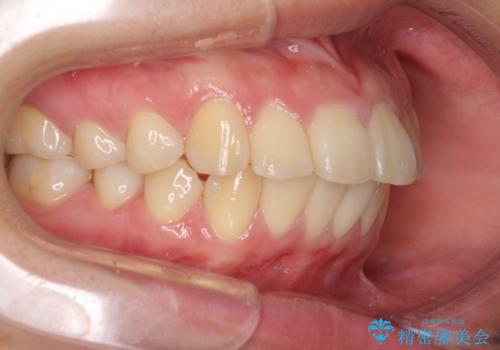

- 上下前歯を部分矯正したところ出っ歯になってしまったとのことで来院された患者様です。

上下左右第一小臼歯4本を抜歯して、積極的に口元を引っ込めるよう、ワイヤー装置にて矯正治療を行うこととしました。

治療後には口が閉じやすくなり、患者様には大変満足していただきました。